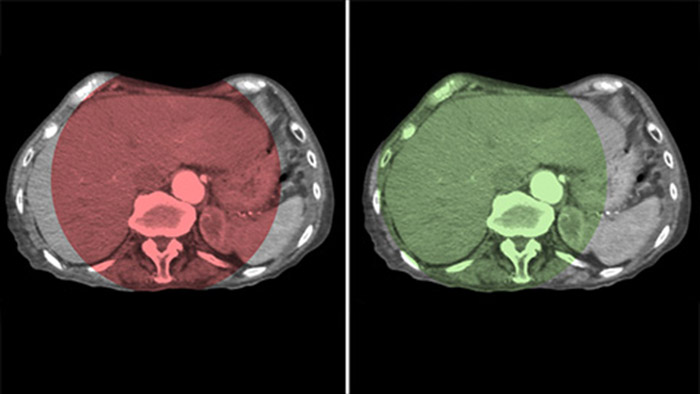

Dual View allows simultaneous visualisation of two CBCT datasets. Both arterial and delayed phase can be displayed next to each other or in a single fused overlay view.

Dual View allows simultaneous visualisation of pre-embolisation arterial phase 3D image and the post embolisation image to assess treatment endpoint.